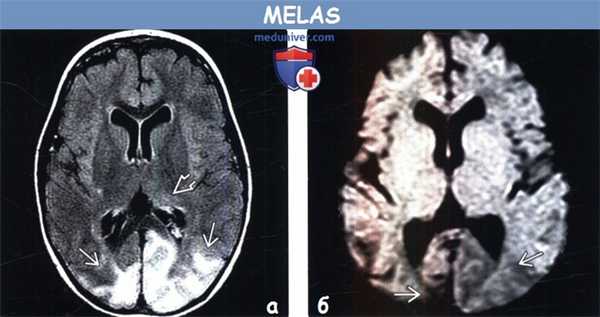

(а) MPT, Т2-ВИ, аксиальный срез: у девочки 12 лет с давним анамнезом MELAS определяется распространенная потеря объема коры и субкортикального белого вещества больших полушарий в сочетании с повышением интенсив нсоти сигнала от перитритонального белого вещества и субкортикального белого вещества/коры теменно-затылочных областей.

(б) МРТ, ДВИ, аксиальный срез: у этого же ребенка отмечается ограничение диффузии в области полюса левой затылочный доли, что указывает на острое поражение на фоне хронических изменений.